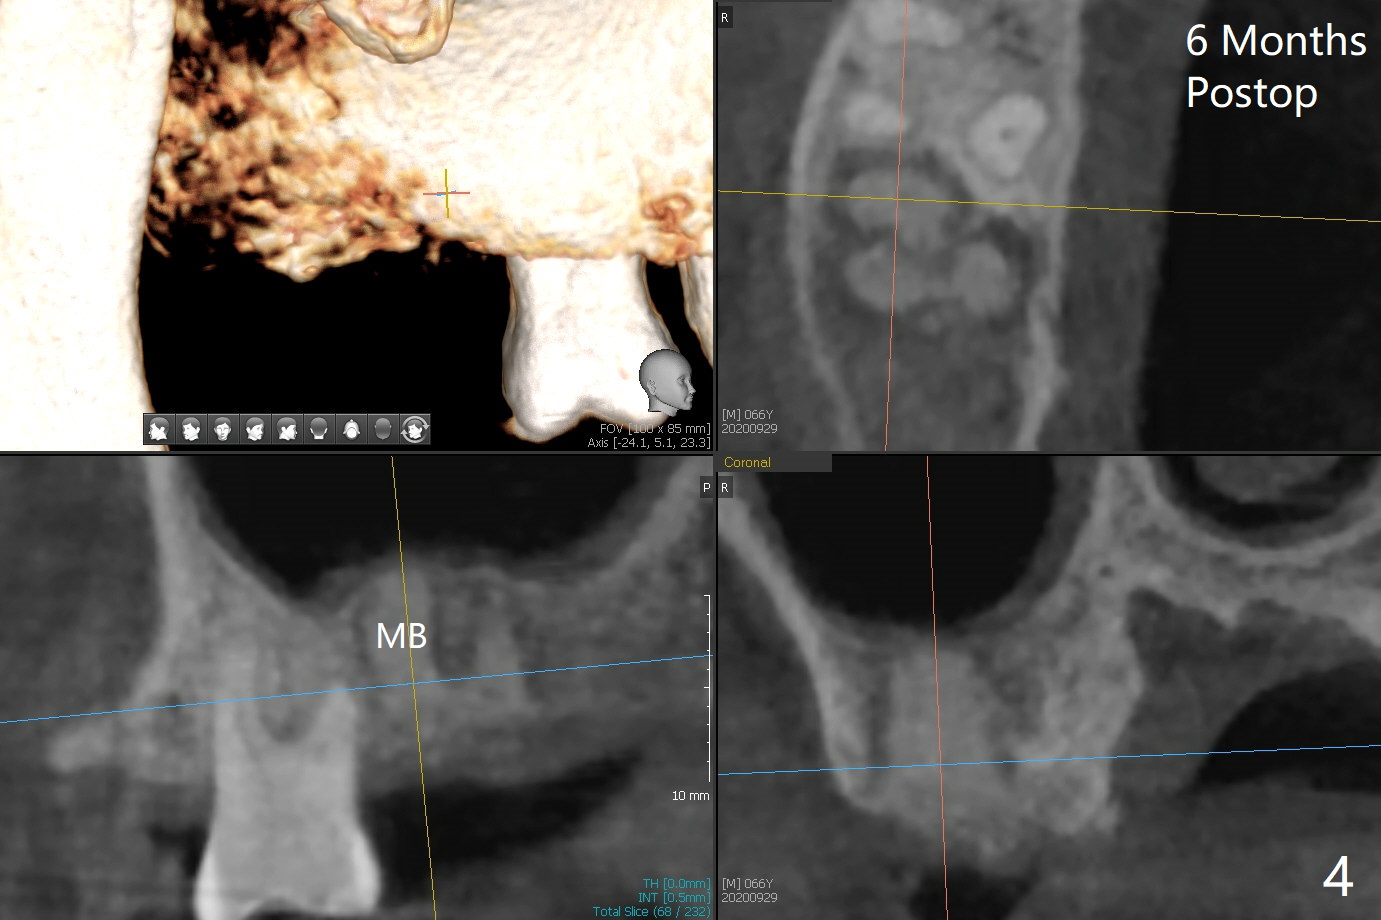

The apices of the mesio-buccal (MB) and disto-buccal (DB) roots are soft when the tooth #2 is extracted. After socket debridement, there is no air leak. Minera-lized cortical and cancellous mix (50/50) hydrated with ~ .25 ml of .3 mg/ml of rhPDGF-BB is placed in MB and DB sockets and pushed upward with a curette. Finally the whole socket is filled up to the crest and a piece of 8x8 mm BioXclude is placed and sutured in placed with 4-0 PGA (Fig.1-3). In fact sinus lift is accomplished moderately MB and DB (Fig.2,3). In fact the density of the bone graft 6 months postop remains the same as immediate postop, similar to the native bone as well (Fig.4,5). With socket preservation, a longer implant will be placed at #2 (Fig.6, as compared 8.5 mm at #15 without bone graft).